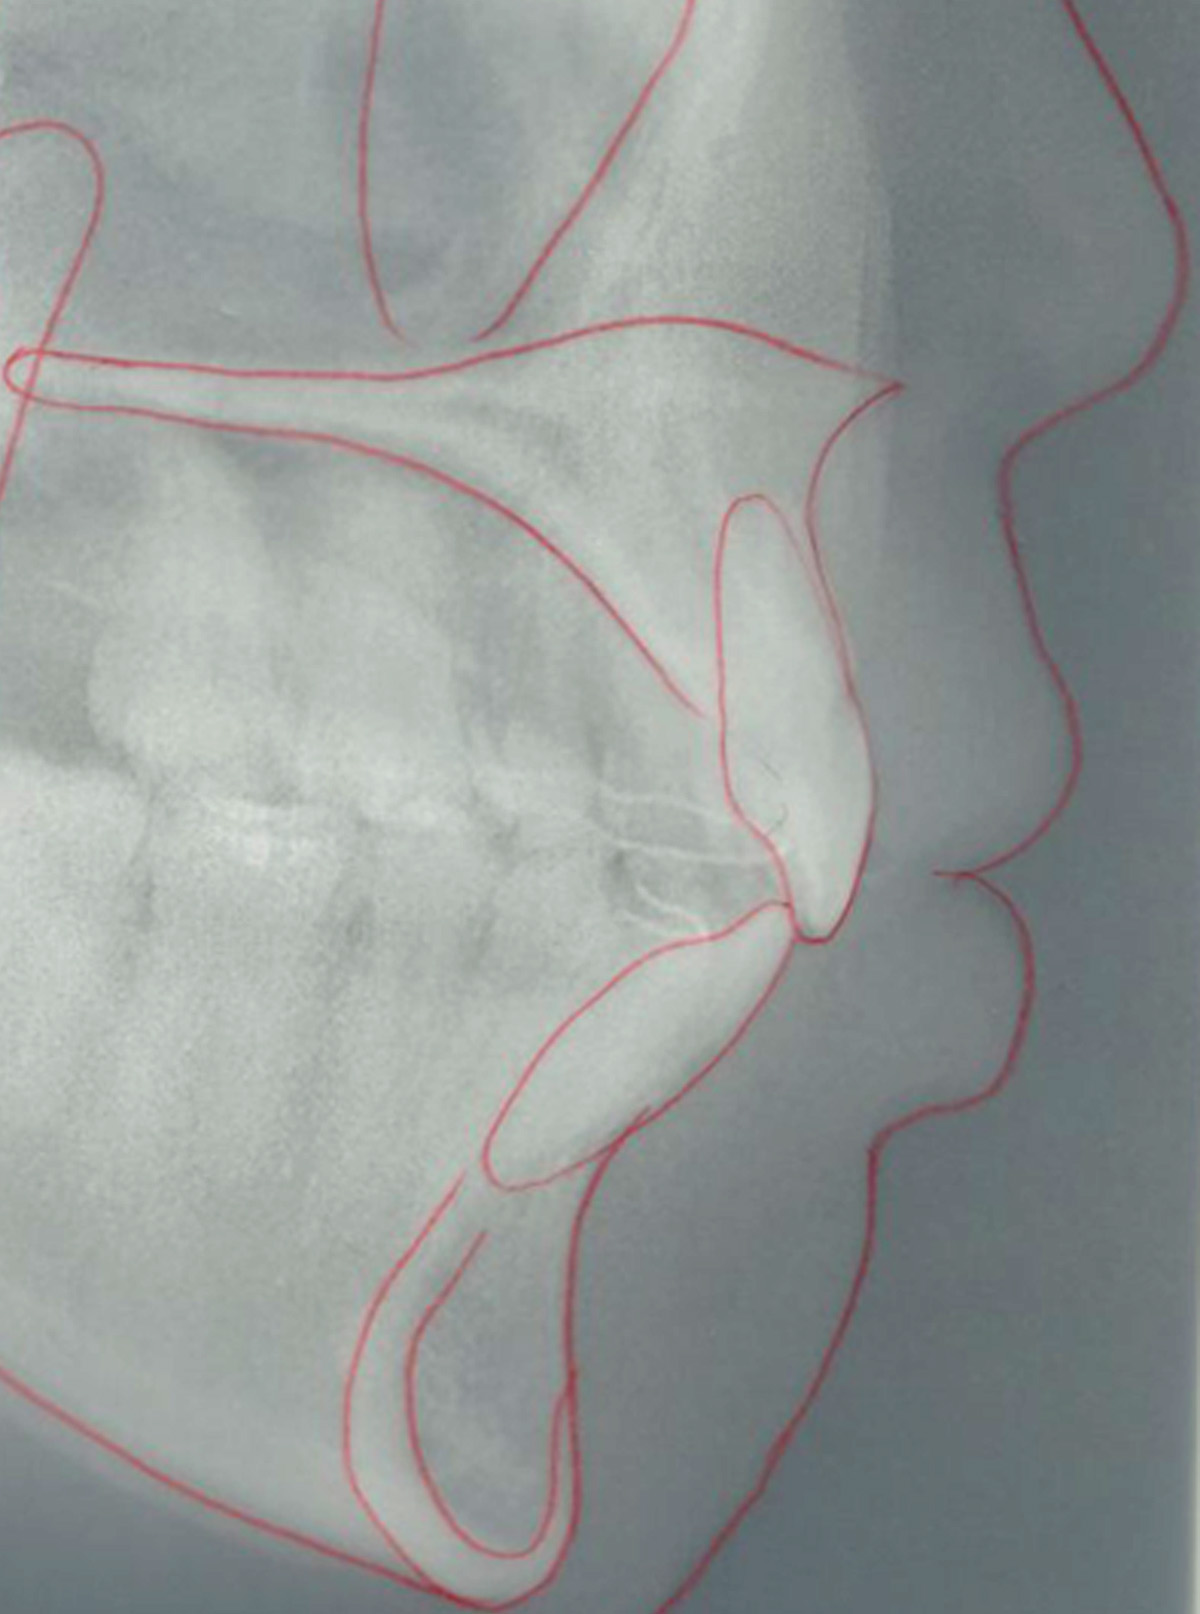

上下顎前突症例

●主訴

歯のデコボコが気になる

●診断

AngleⅠ級・上下顎前突

●治療に用いた主な装置

上顎にリンガルブラケット矯正装置、下顎にマルチブラケット装置(ハーフリンガル)

●抜歯部位

上下左右第一小臼歯

●治療期間

2年6ヶ月

●治療費用

約113万円(ともに税込、調整費、保定費まで含む総額制)